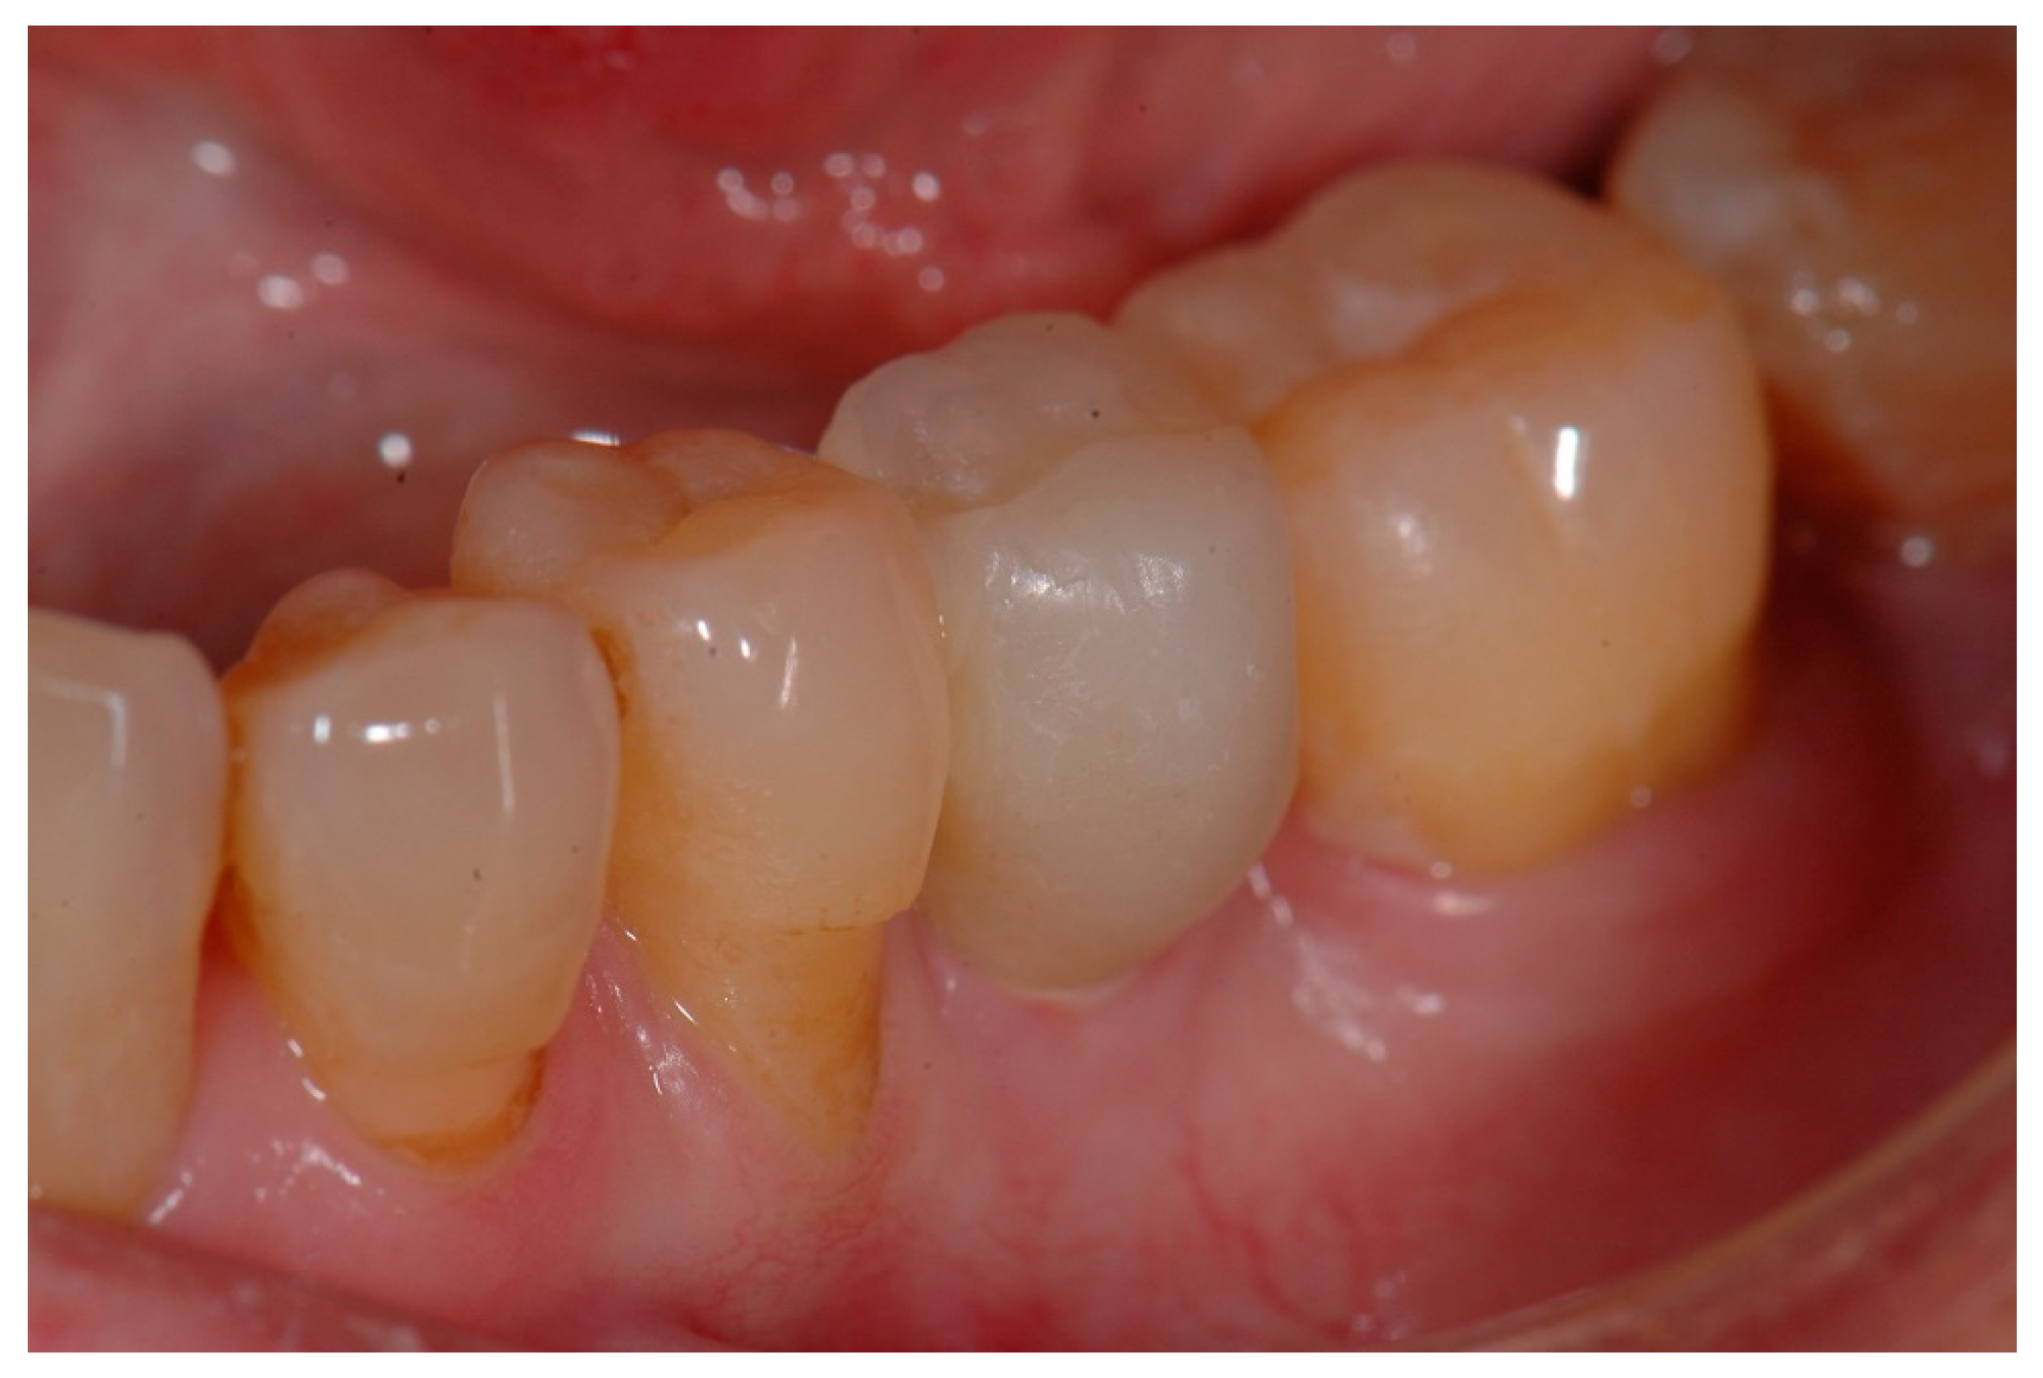

The temporary crown was placed in infraocclusion, ascertaining the absence of occlusal contacts in maximum intercuspidation and during lateral mandibular movements. The gingival implant contours were further adapted by chair-side modifying of the temporary crown. Three months after implant placement, definitive impressions were made using conventional manufacture impression copings. An acrylic try-in was tested and, after laboratory finishing and personalizing, a monolithic zirconia crown was finally cemented using an elastomeric resin cement (Premier® Implant Cement™, Plymouth, MA, USA). Excess cement was carefully removed. Annual follow-up appointments were then scheduled to perform the clinical and radiographic measurements. Figure 5 and Figure 6 illustrate a definitive ceramic nonmetal restoration and the corresponding intraoral X-ray image, respectively, after three years and three months of follow-up.

Lastly, Figure 7 and Figure 8 show a definitive ceramic restoration in another case located in the maxillary left first premolar space and its corresponding intraoral X-ray view, after three years of follow-up.

Figure 5. Definitive ceramic restoration (at 3 years and 3 months of follow-up).